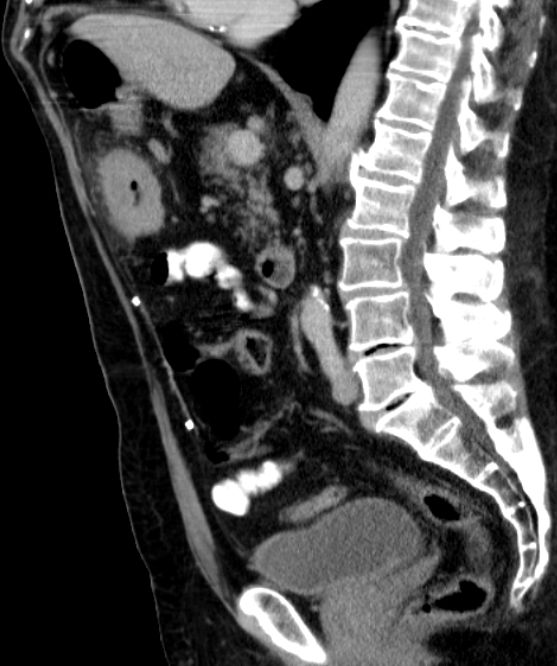

| Colon ascendens | 7-jährige Frau mit Colon ascendes Tumor pT3d pN2a(4/20) L1 Vo.

Großer Tumor mit Infiltration des Fettgewebes. Kein Ileus! |